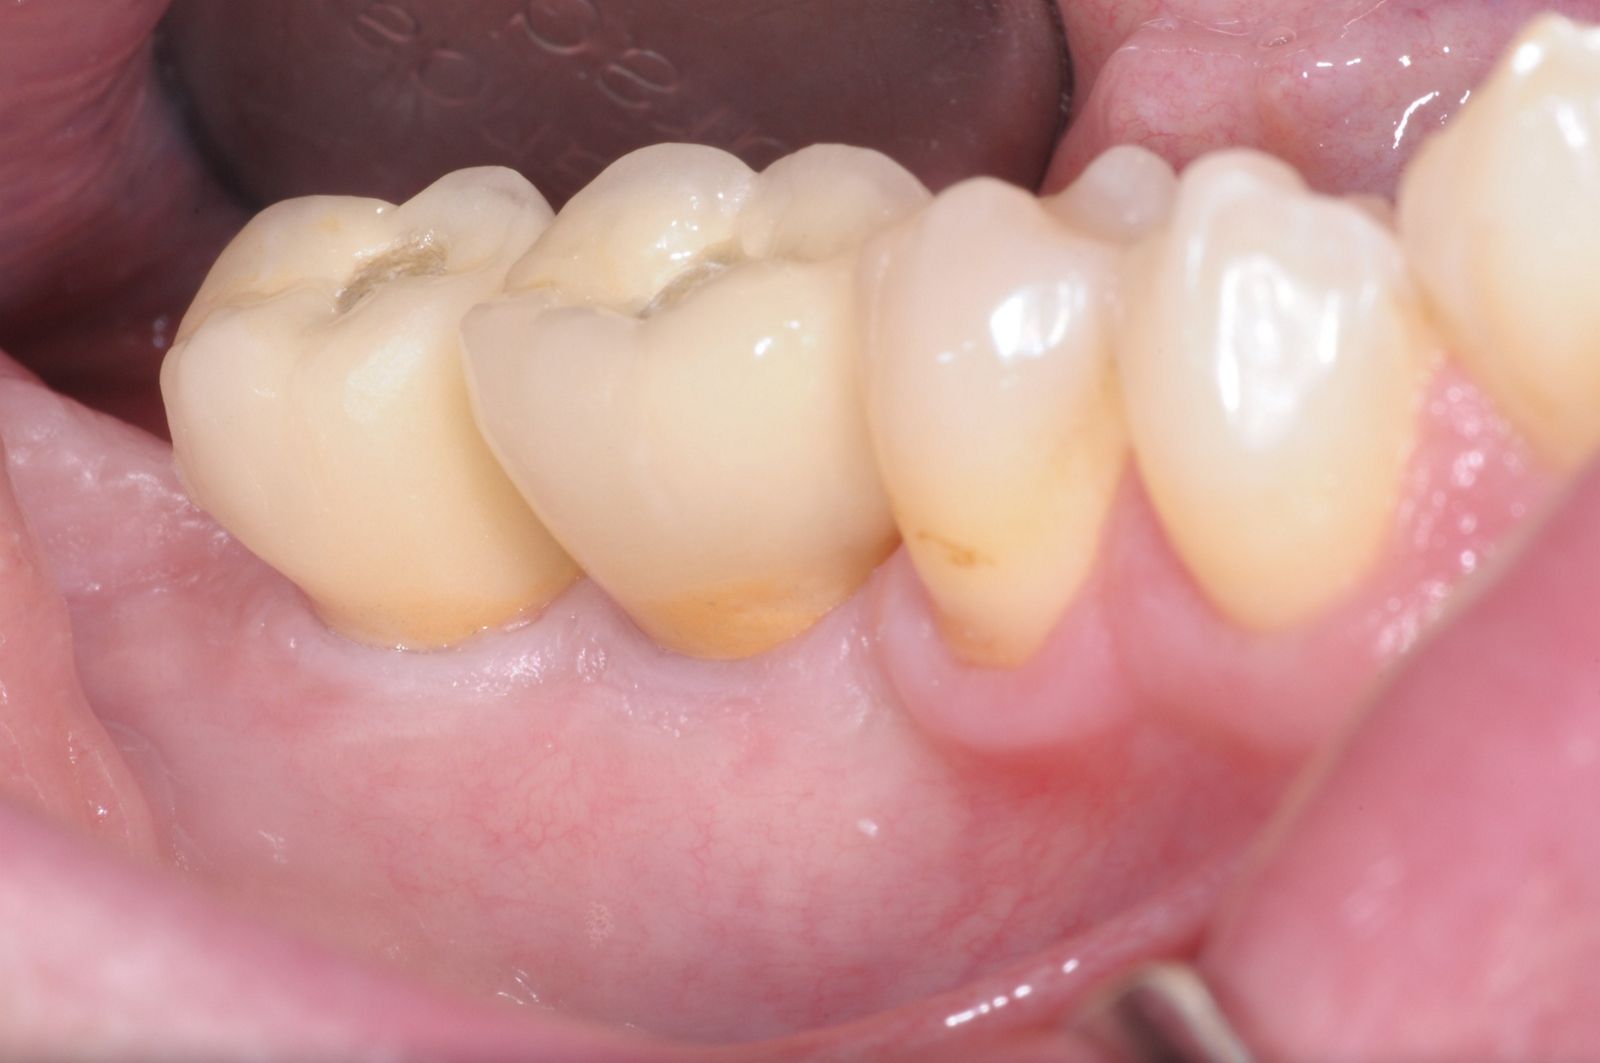

03/28 - Initial clinical situation - massive bone loss in the posterior 4th quadrantThree-dimensional augmentation with maxgraft® cortico - Dr. R. Würdinger

Initial clinical situation: Free end situation in quadrant three and four